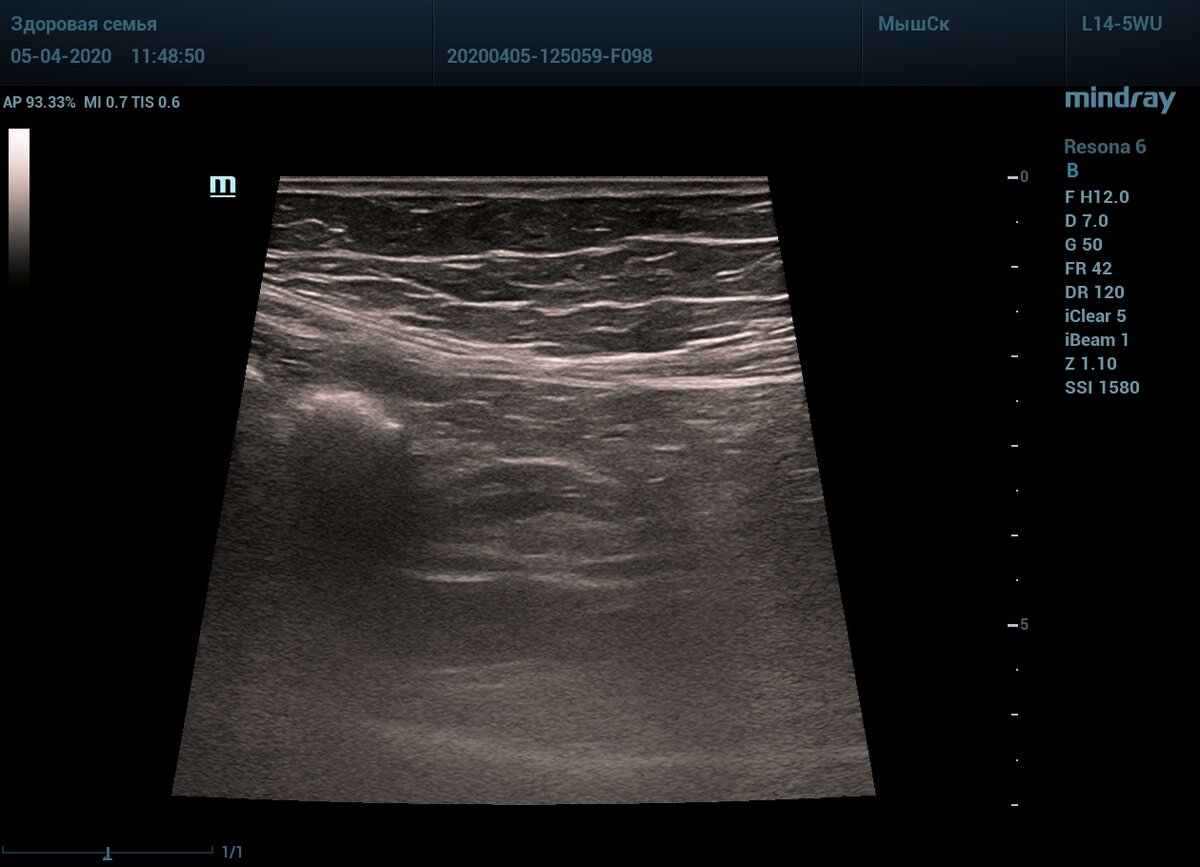

🖼️На снимке купол слепой кишки, заполнен ярким гиперэхогенным газом с тенью. От купола отходит отросток - аппендикс. Нормальная картина.